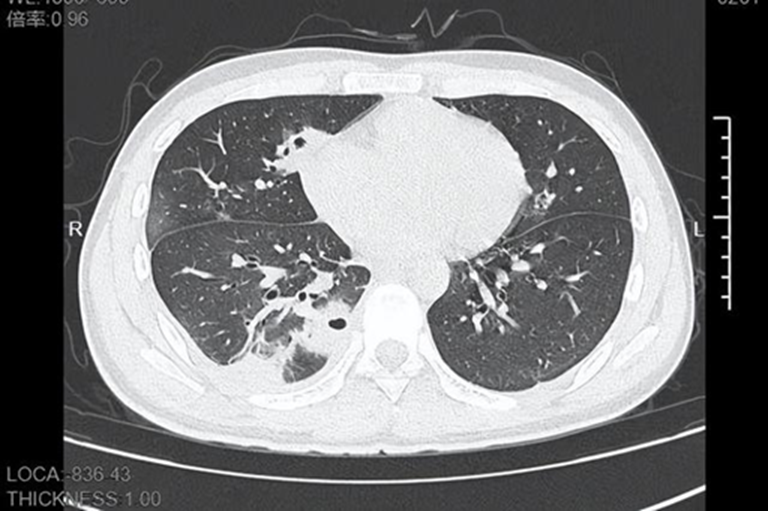

Khi tới bệnh viện, thân nhiệt Lâm đã chạm 39 độ C. CT ngực cho thấy bên trong phổi xuất hiện hơn 10 hốc rỗng , một số vùng mô phổi đã hoại tử, biểu hiện điển hình của áp-xe phổi do vi khuẩn từ đường máu .